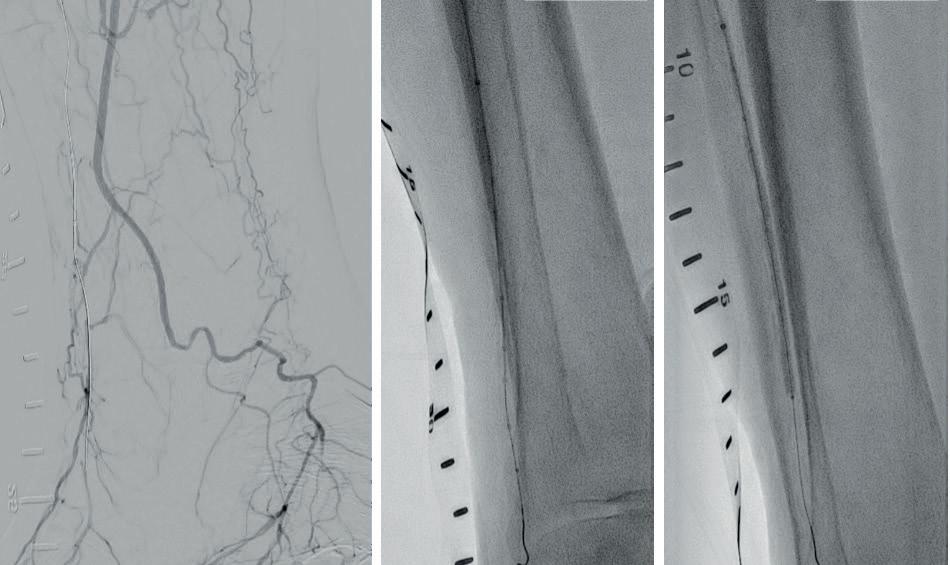

A 75-year-old female patient with diabetes and end-stage kidney disease (ESKD) presented with progressive right second toe swelling ulceration with gangrene and rest pain (Figure 1). There was extensive osteomyelitis and underlying tissue injury which required a planned amputation of the second toe. We were consulted prior to amputation for angiography, which demonstrated patent inflow vessels but severe BTK tibial disease. The baseline angiogram is shown in Figure 2. There was no inline flow to the foot, with occlusion of the anterior tibial, posterior tibial and peroneal arteries (Figure 2a). There was reconstitution of the peroneal artery, with partial filling of the posterior circulation via the posterior communicating artery. There was reconstitution of the anterior circulation with a visible small dorsalis pedis artery (Figure 2b).

Procedural overview

Given the angiosome of the tissue loss, we elected to pursue opening the anterior tibial CTO. Access with a 5F, 70cm sheath was used from a contralateral femoral approach. Using a 0.014” microcatheter and wire escalation, we were able to cross into the true distal lumen of the distal anterior tibial circulation using a 12-gram tipped guidewire (Figure 3a). A 2.5mm Shockwave E8 was used for multiple treatments along the entire length of the CTO segment (Figures 3b, 3c). Post IVL therapy, angiography showed brisk flow through the anterior tibial and into the distal anterior circulation of the foot (Figures 4a-c). This improvement in circulation allowed for this patient to undergo her planned second toe amputation with primary close (Figure 4d).